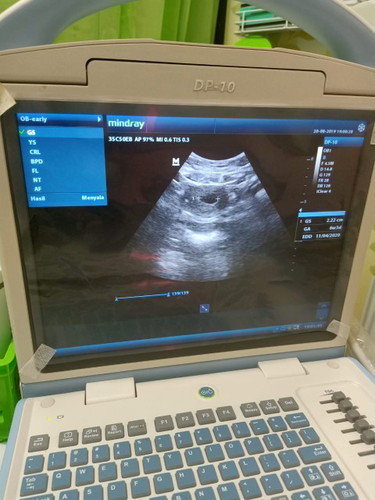

bun mau tanya nih.... saya hamil anak pertama uk 6 mgg 4 hari... semalam saya USG tapi yg terlihat baru kantung kehamilan saja? apa itu wajar bun? apakah para bunda ada yg sma sperti saya? ?